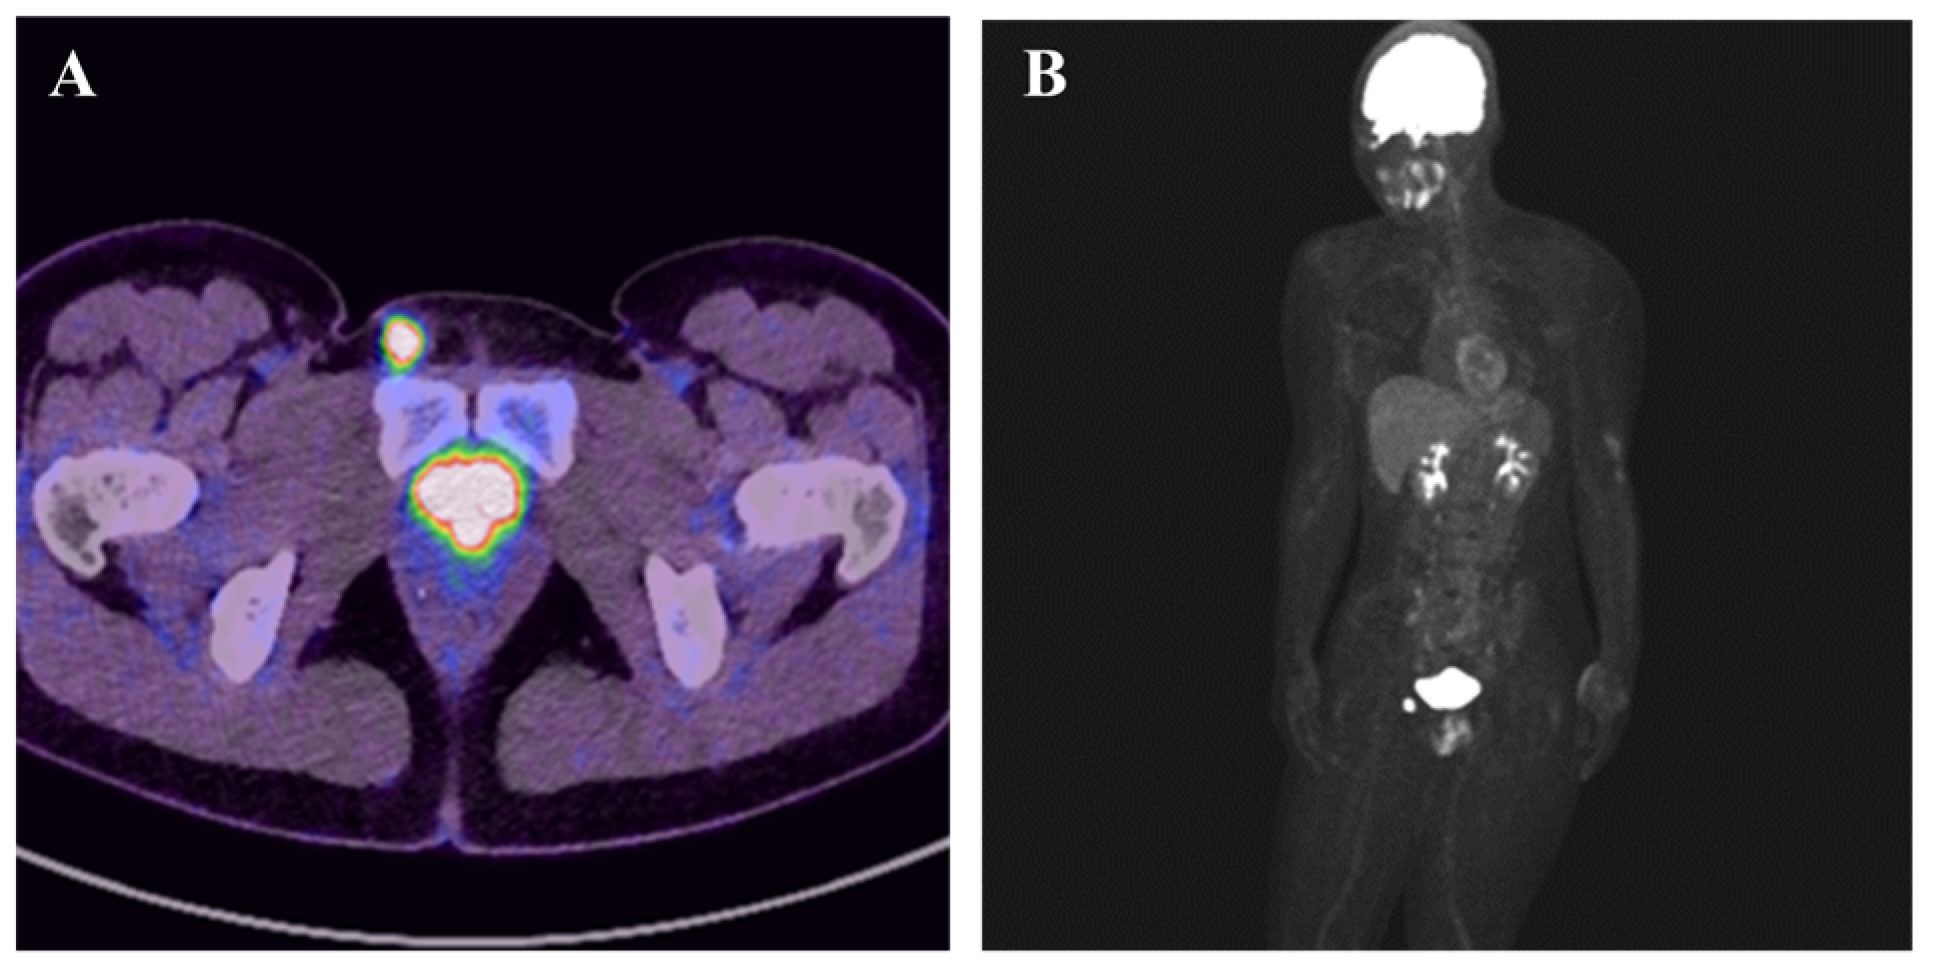

Proximal Epithelioid Sarcoma Mimicking Inguinal Inflammation

Kawasaki, T.; Watanabe, T.; Kanno, S.; Torigoe, T.; Onohara, K.; Wako, M.; Hagino, T.; Ichikawa, J. Proximal Epithelioid Sarcoma Mimicking Inguinal Inflammation. Diagnostics 2025, 15, 2246. https://doi.org/10.3390/diagnostics15172246